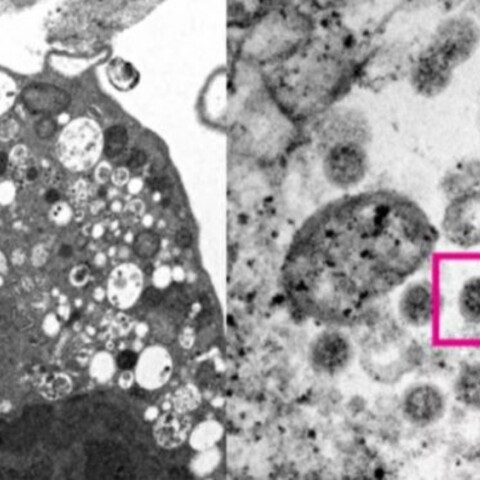

Μετάλλαξη Όμικρον: Η πρώτη φωτογραφία από ηλεκτρονικό μικροσκόπιο

Την έλαβαν από κύτταρο του νεφρού ενός πιθήκου